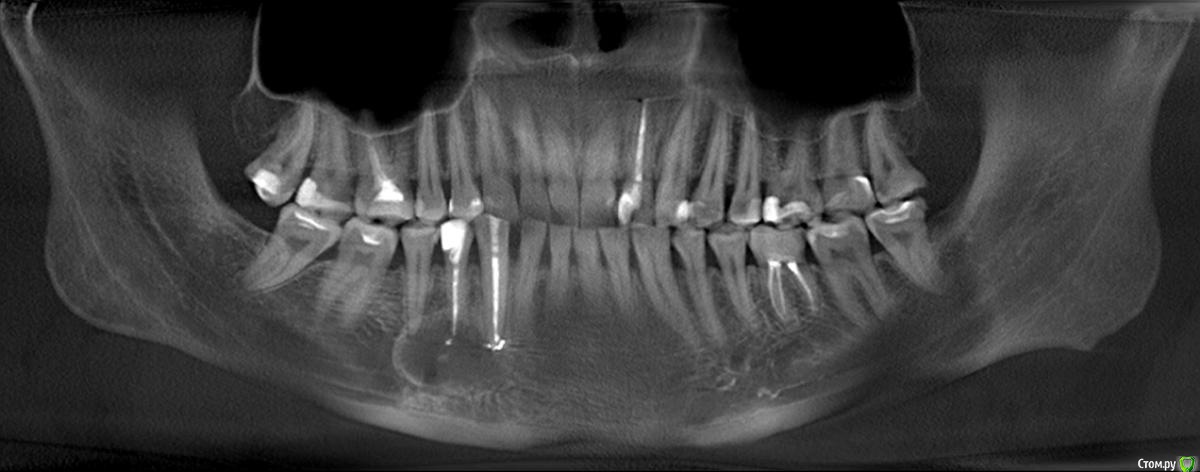

sewif Опубликовано 5 июня, 2020 Автор Поделиться Опубликовано 5 июня, 2020 (изменено) ЗдравствуйтеСегодня сделал контрольное КТ. После лечения прошло где-то 5-5,5 месяцев. КТ делал в одной клинике, а доктор который лечит зубы работает в другой клинике (к нему визит послезавтра) . В клинике в которой делал КТ, работает ЧЛХ из Моники, я к нему сразу на консультацию и записался. Мнение хирурга:1) По верхней кисте заметная положительная динамика.2) По нижней кисте: непонятно. Далее пишу сумбурно, в голове каша но как я понял: похоже на то, что жидкость из кисты ушла. Киста "скукожилась" и что-то в ней образовалось (непонятно что..фиброз? или что-то другое). Также сказала, чтобы врач внимательно посмотрел 5 зуб...возможно его стоит тоже депульпировать.Вердикт: ждать еще 3 месяца. Также сказала, что если бы она не видела снимок от октября 2019г...то по текущему снимку, сказала бы что у меня не кисты, а другие болячки с зубами....по нижней амеоба-чего-то там Первый снимок от 24 октября 2019Второй снимок от 05 июня 2020 Изменено 5 июня, 2020 пользователем sewif Ссылка на комментарий

Irouil Опубликовано 5 июня, 2020 Поделиться Опубликовано 5 июня, 2020 Есть положительная динамика и наверху, и внизу Ссылка на комментарий

Bier Опубликовано 5 июня, 2020 Поделиться Опубликовано 5 июня, 2020 на мой взгляд явное улучшение и вверху и внизу Ссылка на комментарий